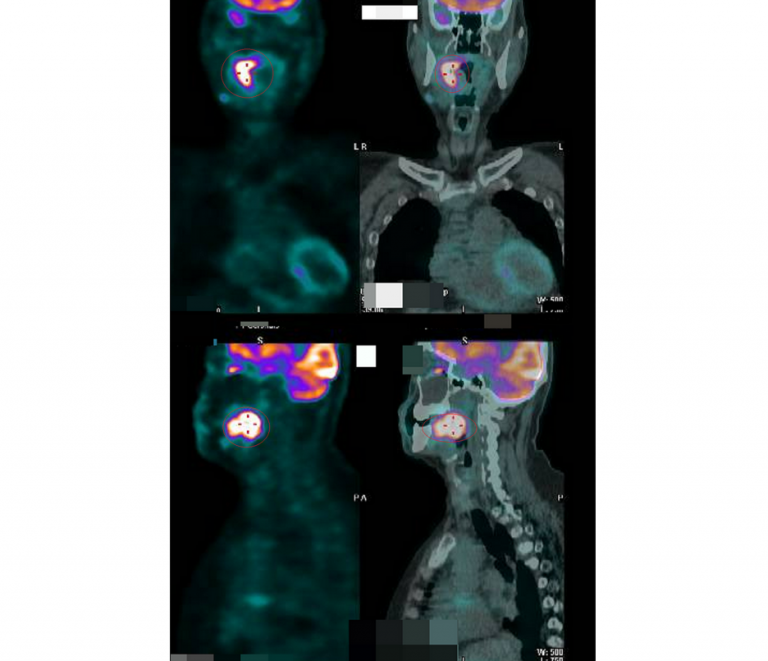

▲父母發覺她聲音沙啞及進食有困難的模樣,經過多項檢查及正子攝影,發現在咽喉處有個5.1公分的腫瘤,並確定為第4期的末期癌症。(圖╱彰化醫院提供)

張博竣說,程女患有思覺失調症,有妄想及幻聽、幻覺的症狀,雖然服藥治療,但其服藥順從性不佳,也使得病情反反覆覆,在幾個月前,她被父母帶來就醫,因為父母發覺她聲音沙啞及進食有困難的模樣,經過多項檢查及正子攝影,發現在咽喉處有個5.1公分的腫瘤,並確定為第4期的末期癌症。

▲患者做了5次化療,並進行了35次的光子刀治療,以高精準度直線加速器,對病灶精確定位,做高劑量放射,療程結束後,腫瘤壞死萎縮,但後續還要定期追蹤。(圖╱彰化醫院提供)

張博竣說,程女向醫護人表示如果她接受治療,會被邪體搞死,父母也勸說不動,他們以耐心及同理心和程女溝通好一段日子,她才願意接受治療。他們對程女做了5次化療,並進行了35次的光子刀治療,以高精準度直線加速器,對病灶精確定位,做高劑量放射,療程結束後,腫瘤壞死萎縮,但後續還要定期追蹤。